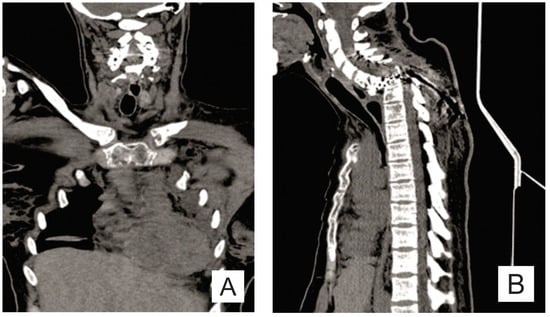

| Month I | C7 corpectomy and reconstruction with autologous graft from the iliac crest, macroscopic resection of the posterior arches C7-T1 and fixation with C4-C5-T3-T4 cervico-thoracic hybrid system |

| Month III | Ablation of osteosynthesis material and bone graft and T1 corpectomy, reconstruction with C6-T1 mesh fixed with proximal and distal screw |

| Month IX | Ablation of damaged osteosynthesis material mesh C6-T1, ablation of thoracic screws, and introduction of bilateral T3, T4, and T5 screws |